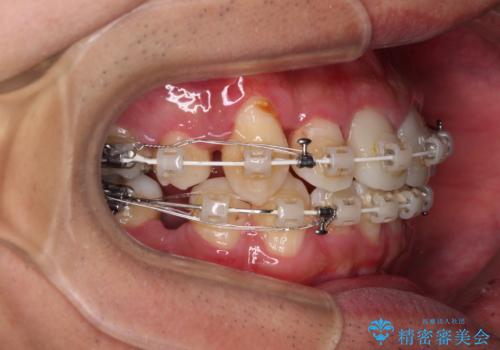

- 矯正装置

- 審美装置

上下ともに八重歯が顕著であったため、上下左右の第一小臼歯4本を抜歯し、ワイヤー装置での抜歯矯正を行うこととしました。

前歯は根管治療が必要な歯を事前に根管治療を行い、矯正治療後にオールセラミッククラウンにて補綴治療を行うこととしました。